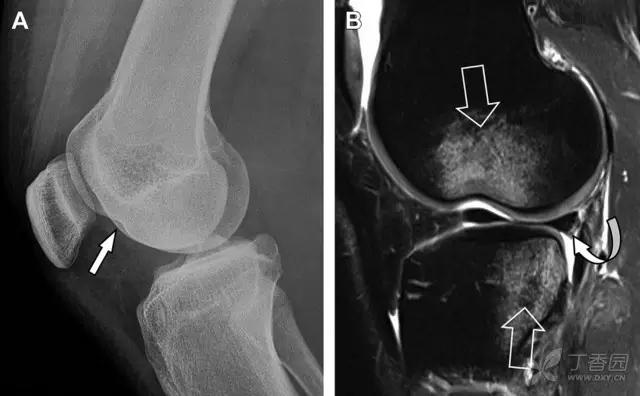

9 股骨外侧髁凹陷征

图 2 扭伤后的股骨外侧髁凹陷征

A 侧位片示股骨外侧髁凹陷。B MRI 矢状位 T2 加权像示股骨外侧髁及胫骨后外侧骨挫伤(空箭头)。胫骨近端随着后交叉韧带撕裂发生移位,露出外侧半月板的后角(弧形箭头)。